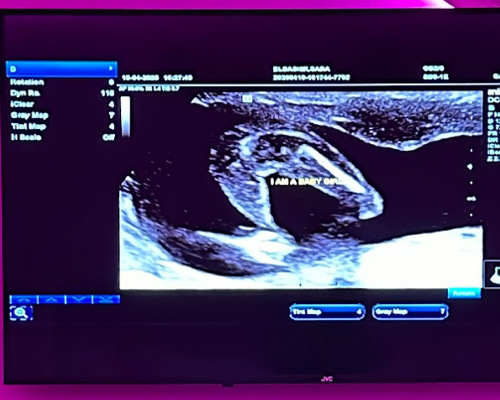

During an appointment, a trained sonographer uses a small handheld device known as a transducer. This is gently moved across the abdomen, sending sound waves into the body. As these waves return, they are transformed into images displayed on a screen in real time.

At the beginning, a small amount of gel is applied to the abdomen. This helps the probe glide smoothly and improves image clarity. The sonographer will then gently move the probe across the area while images appear instantly on the screen.

Depending on the stage, you may be able to see movement, positioning and heartbeat during the scan. The sonographer will talk you through what is visible and answer any questions along the way.